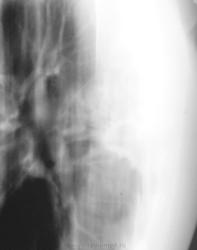

Решили "чиркнуть" боковые томограммы.

ну,если учесть, что у пациента и справа была такая же ерундистика, то скорее туберкулез, а почему не делаете КТ ? нет возможности?

Контроль еще через 1 месяц.

В облтубе пациента решили прооперировать.

тень овальной формы в подключичном отделе слева туберкулёзной природы. Не исключаю наличие лекарственной устойчивости МБТ к противотуберкулезным препаратам и, как следствие, прогрессирование процесса в лёгких. Возможно, неадекватная терапия? Сочетанная патология в 43 года редкость. Я убежден в правильности тезиса русского клинициста М.Я.Мудрова: "Ищи одну болезнь", который не раз в моей практике подтверждался. На сайте нетипичные случаи демонстрируюся достаточно часто, которые расширяют кругозор многих врачей. Данный случай может попасть в нетипичную группу. Но, так ли окажется? После #22 стало трудно. Буду ждать мнений других участников. Высказвайтесь господа. Сайт бесплатный!

Да, после удаления, верификация - туберкулома.